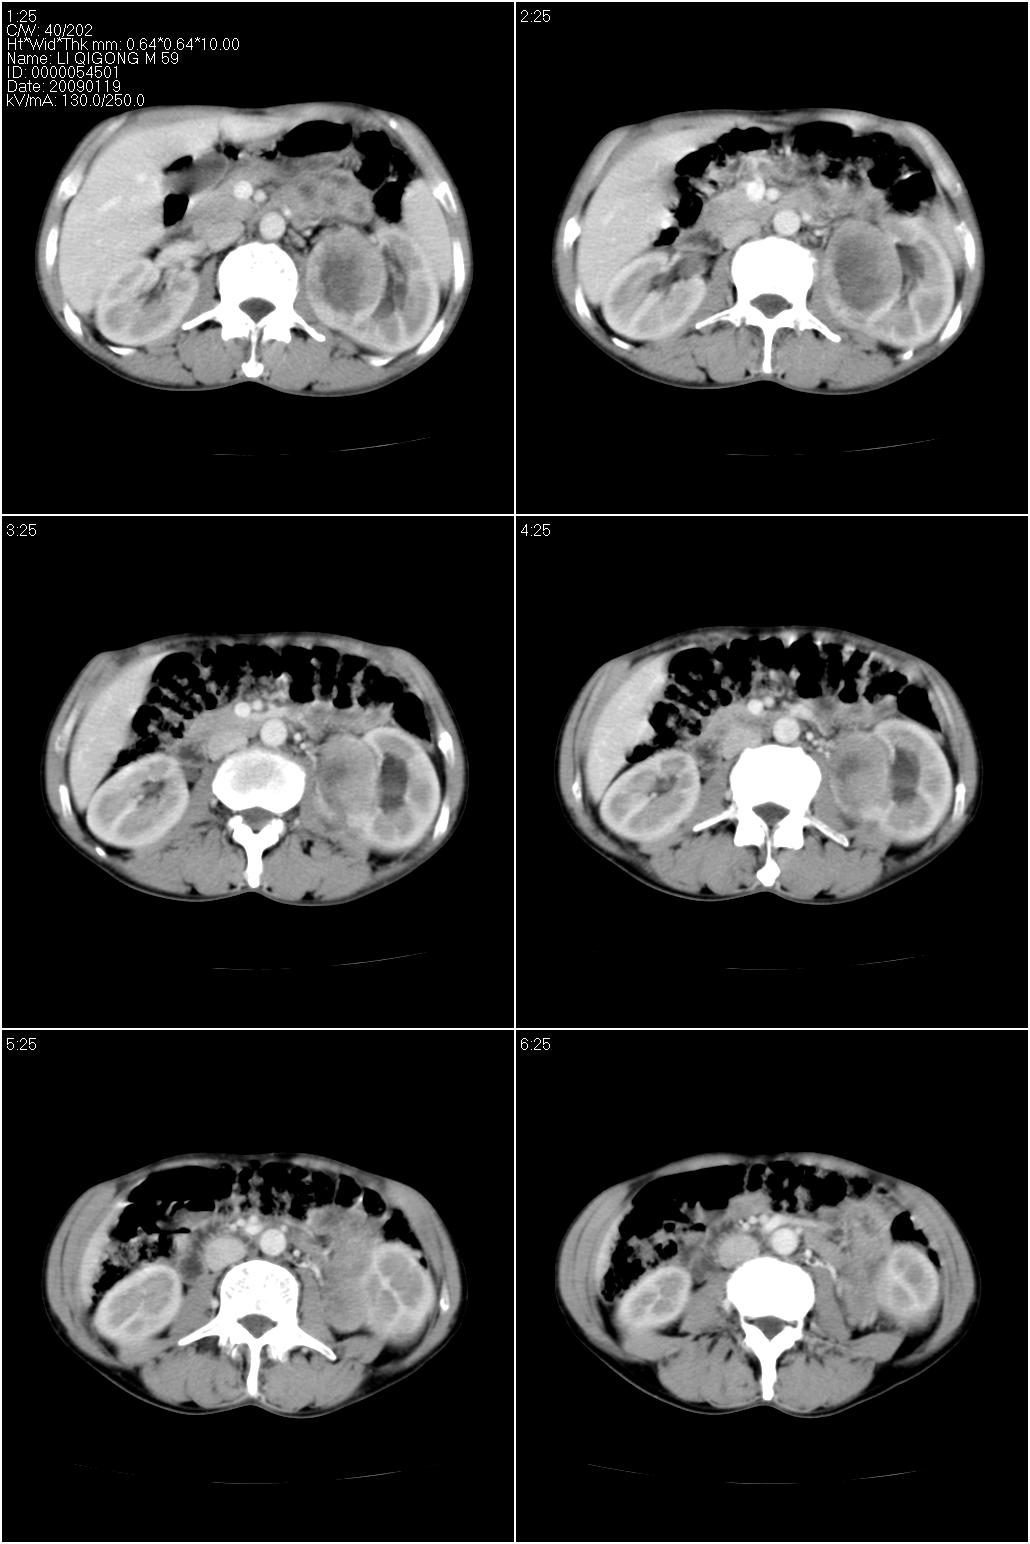

男性,59岁。体检发现左肾占位。自诉无尿血、尿痛。

无痛无血尿,左肾实质占位,有明显强化,中心坏死不规则,应该肾癌无疑。

应该考虑左肾癌并肾盂积水

诊断依据:

1、中老年男性.

2、左肾占位,呈不均匀性强化,中央有无强化的坏死区。

3、左肾门旁有侧枝开放,提示左肾静脉癌栓形成可能。

4、患者自诉无血尿,但不一定镜下无血尿。